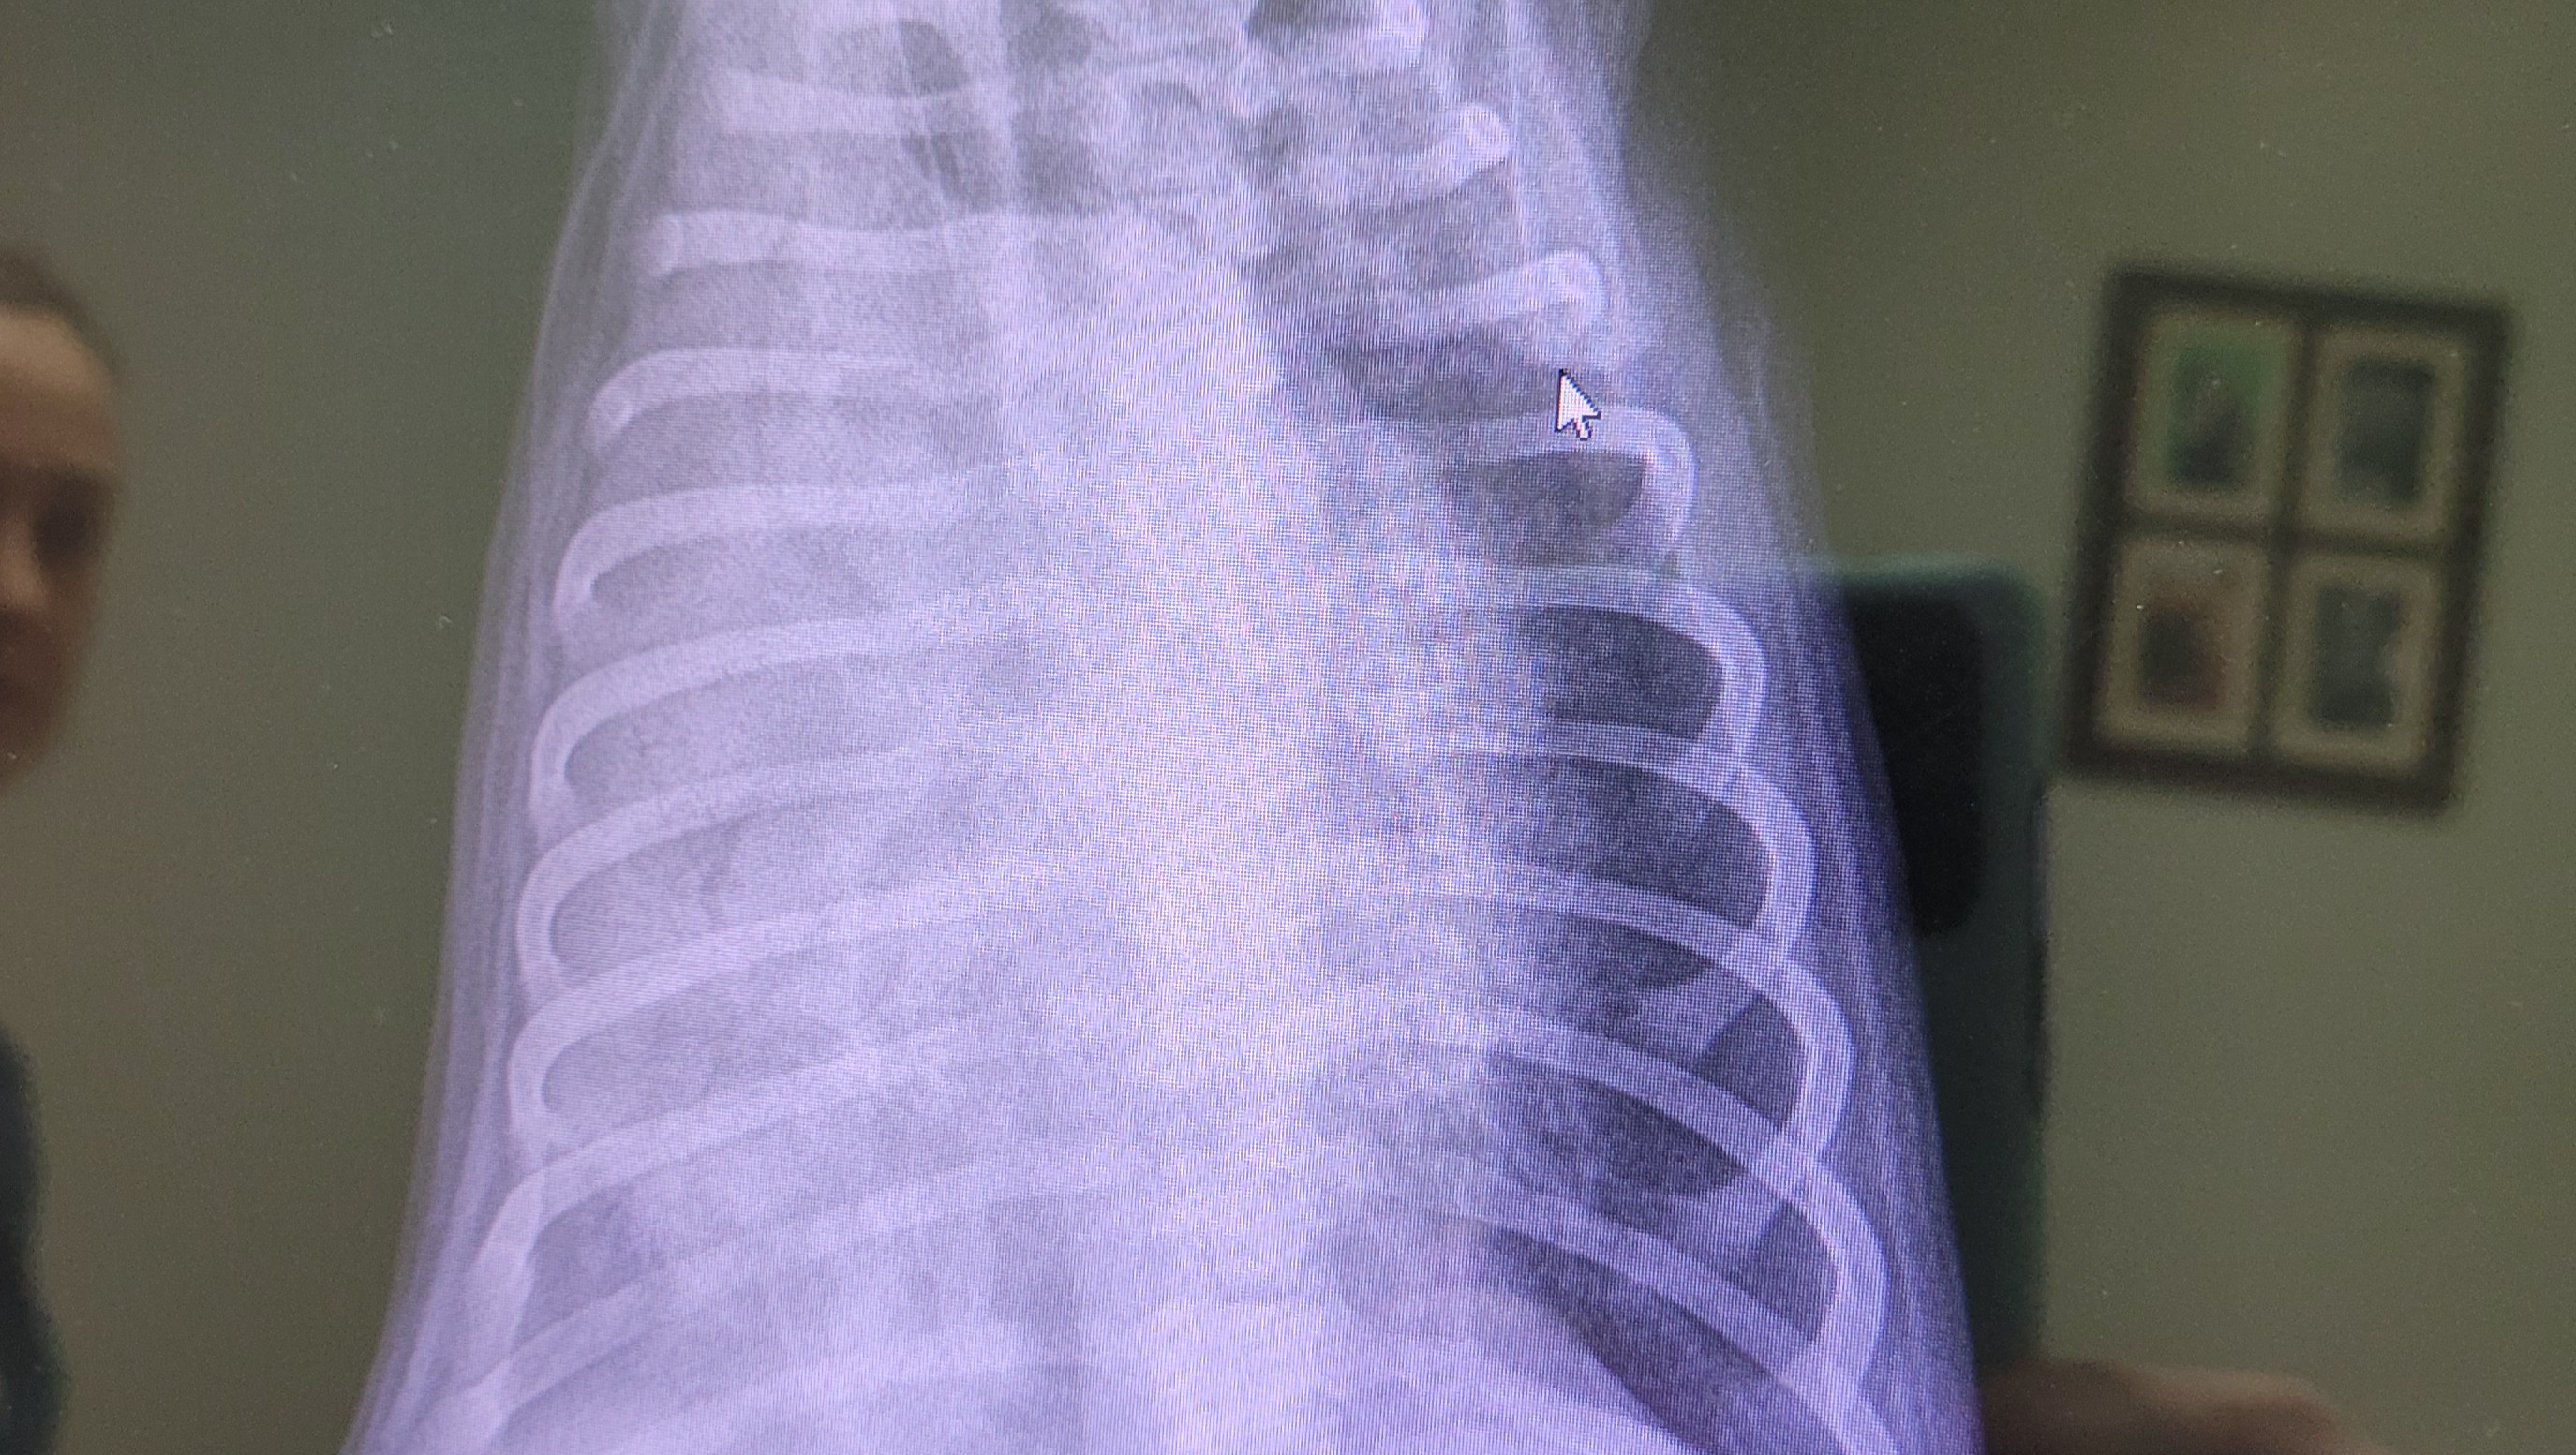

We got her an emergency vet appointment on Friday, where she was found to have a significant fever and a very bad right sided pneumonia. She was transferred to a hospital capable of keeping her overnight and giving her oxygen and IV antibiotics.